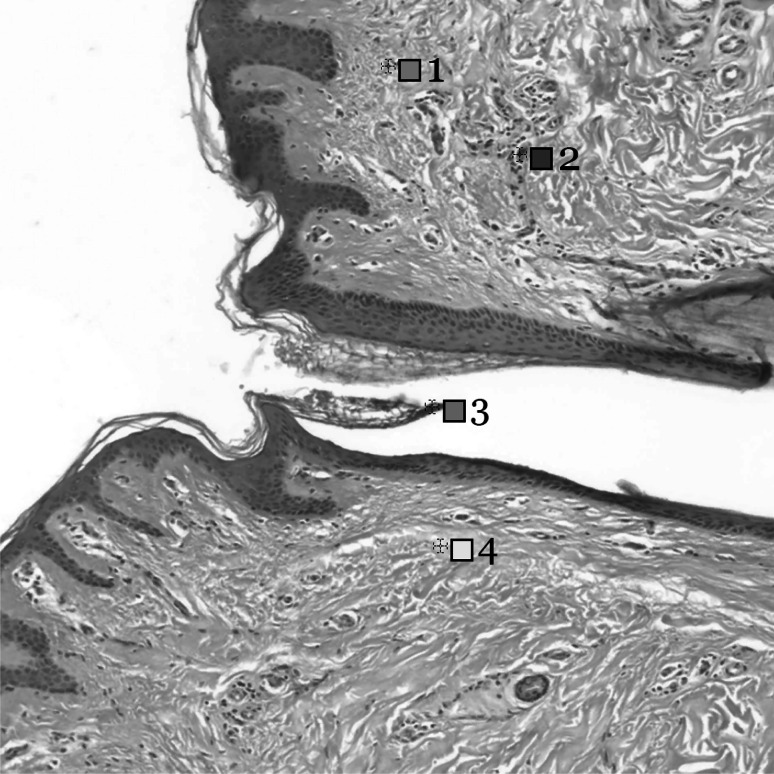

In the first experiment, each of the 24 color patches from ColorChecker was rendered through the five configurations (Table 2) and then sampled as a single-frame, 1024x1024 pixel PNG image with four channels for each R, G, B color and alpha. Values in sRGB color space were input via the Albedo property found in the material’s shader script for each of the 24 color patches. In the second experiment, a single-slide tissue sample obtained from multispectral imaging [8] was imported into Unity as a 2D texture file. Four pixels of varying RGB values were selected from the ground truth image (Figure 3) and then compared with the render result through the same five configurations.

Fig. 3.

Four pixels varying in RGB values are selected from the ground truth of a tissue sample slide obtained from multispectral imaging [8] as input RGB data

Experiment 2: Tissue WSI

The ground truth of a skin tissue slide sample obtained from multispectral whole-slide imaging (WSI) [8] was imported into Unity as a 2D texture file. Import settings were kept at default values. The four chosen pixels varying in RGB values (Fig. 3) were then rendered through the five rendering configurations as in the first experiment. values ranged from 7.49 to 34.18 (Fig. 5b). Unlike in the Experiment 1: ColorChecker results, the Unlit configuration in this experiment did not return zero values of . Rather, the Unlit configuration resulted in the highest values in three of four selected pixels in a skin tissue sample image. These results are unexpected and do not exhibit any of the patterns or increasing trends seen in the first experiment despite consistency in methods.